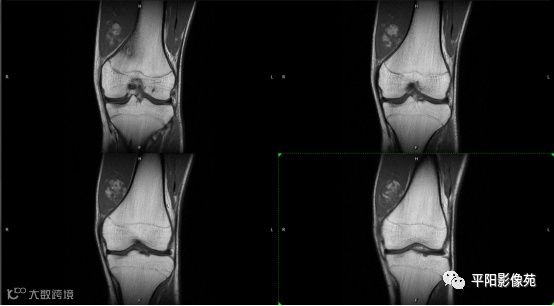

影像表现:

左膝关节股内侧肌内见多房样短T1长T2信号,内可见分隔,增强扫描明显强化,分隔未见明显强化,病灶局部与股骨远端分界不清。